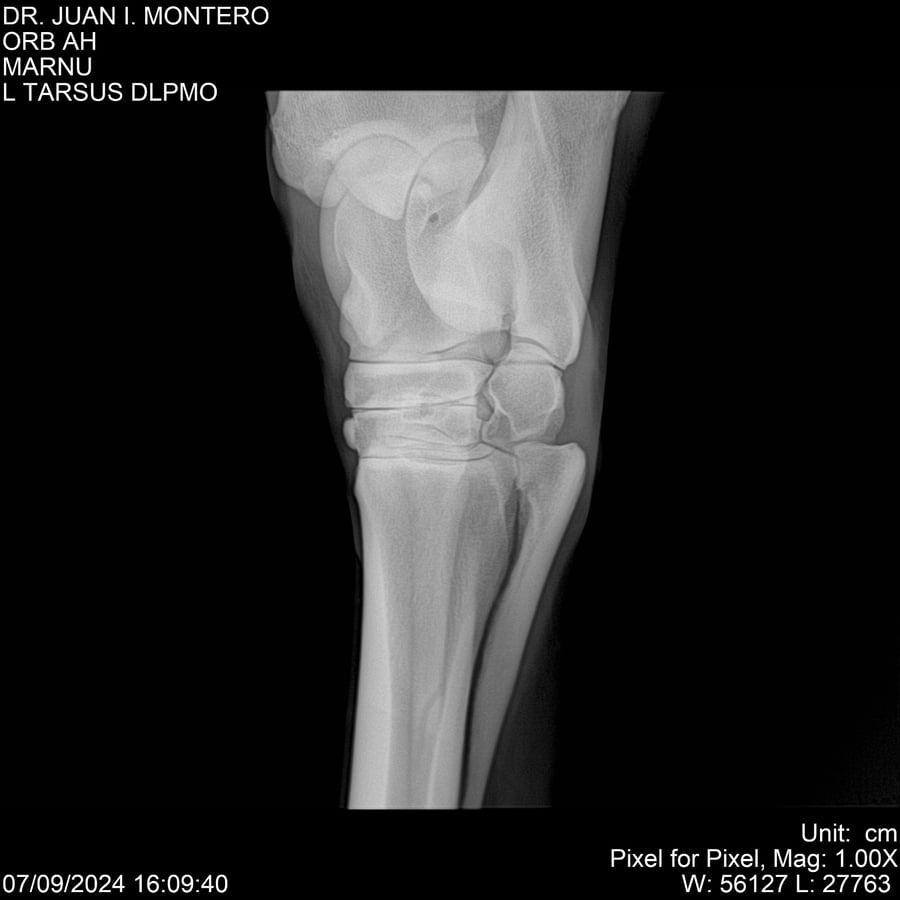

LOTE 21, ORB AH Lote Anterior Volver al remate Lote Siguiente Ficha Contacto Montevideo - Ficha del Lote Identificador: #282519 Categoría: Yeguarizos Montevideo - 57 Visualizaciones ClicData Contacto Empresa: Abelenda N. R., Walter Hugo Nombre*: Teléfono* : E-mail* : Mensaje Enviar Registrese gratis Este contenido Exclusivo está disponible sólo para usuarios registrados Ingresar